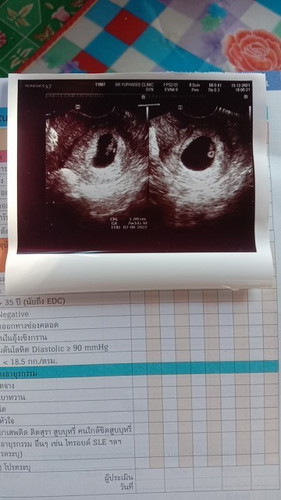

เมื่อวานไปฝากครรภ์ 7w1d ซาวด์ทางช่องคลอดเพราะซาวด์ที่ท้องไม่เห็นอะไรเลย อยากถามแม่ๆว่าเพราะอะไรค่ะ เคยซาวด์ทางช่องคลอดรึป่าวคะ

ซาวด์ครั้งแรกเลยค่ะตอนที่รู้ว่าตั้งครรภ์ก็ไปหาหมอ หมอเลยซาวด์ทางช่องคลอด เพราะน้องตัวเล็กมากๆ หมอจะตรวจดูถุงตั้งครรภ์ด้วยว่ามีตัวอ่อนรึเปล่า ของเราเห็นชัดเจนเลยค่ะ ตอนนั้น6วีค และตอนนี้21วีคแล้วค่ะ😊😍

อาจจะเป็นเพราะอายุครรภ์ยังน้อยนะคะ บ้านนี้ก็เคยค่ะ ซาวด์ตอน 5 วีคค่ะ ทั้งหน้าท้องและช่องคลอด เพราะไม่เจอตัวอ่อน เจอแต่ถุง พอ 8 วีค เจอทั้งตัวอ่อนทั้งเสียงหัวใจเลยค่ะ ตอนนี้ 35 วีคแล้วค่ะ

ตอนอายุครรภ์ 5 -7 สัปดาห์ ซาวด์ทางช่องคลอดเหมือนกันค่ะ เพราะยังเล็กส่องทางท้องไม่เห็น คิดว่าน่าจะเป็นเรื่องปกตินะคะ สัปดาห์ที่ 8 เริ่มซาวด์ทางหน้าท้องเห็นบ้างละคะ แต่ยังไม่ชัดเท่าไหร่

เพราะอายุครรภ์ยังน้อยอยู่ค่ะ จึงต้องซาวด์ผ่านทางช่องคลอด. แต่ถ้าอายุครรภ์เพิ่มขึ้นมาอีกหน่อย,ซักประมาณ10สัปดาห์ ซาวด์ผ่านหน้าท้องก็จะเริ่มเห็นเป็นตัวเด็กแล้วค่ะ

ครั้งแรกไปฝากครรภ์ตอนนั้น5วีคค่ะ หมอซาวด์ทางช่องคลอดให้เจอถุงตั้งครรภ์ เดือนต่อมา8วีค5วัน หมอก็ซาวด์ทางหน้าท้องเห็นน้องพร้อมเสียงหัวใจแล้วค่ะ

เราซาวตอนน้องได้ 6wค่ะผ่านช่องคลอดเช่นกันเพราะถ้าผ่านหน้าท้องจะยังไม่เห็นตัวน้องค่ะเพราะน้องเล็กอยู่ ของเรามีเสียงหัวใจด้วยค่ะ

ซาวด์หน้าท้องไม่เจอเหมือนกันคะ ต้องซาวด์ทางช่องครอด พบหัวใจน้องคะ ผ่านไป3อาทิตย์หมนัดซาวด์อีกรอบ พบน้องแฝดคะ